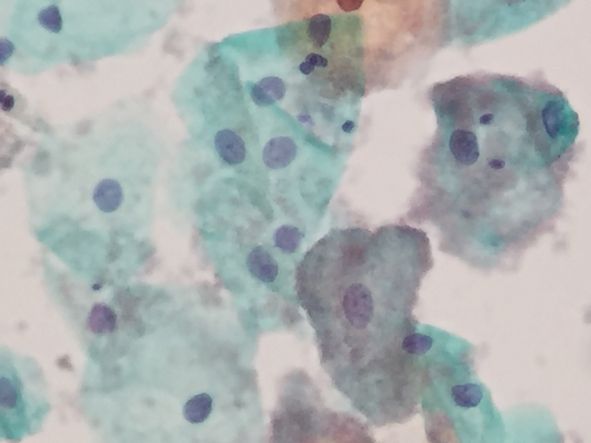

ところが、同じ分泌期のケースですが、前の写真とは全く異なり、中央やや右に紫っぽく染まる細胞がみられますが、これはクルーセルといいます。小さな菌が細胞に群がった状態ですが、細胞の上だけでなく写真全面に散らばっています。乳酸菌とは全く違った菌です。